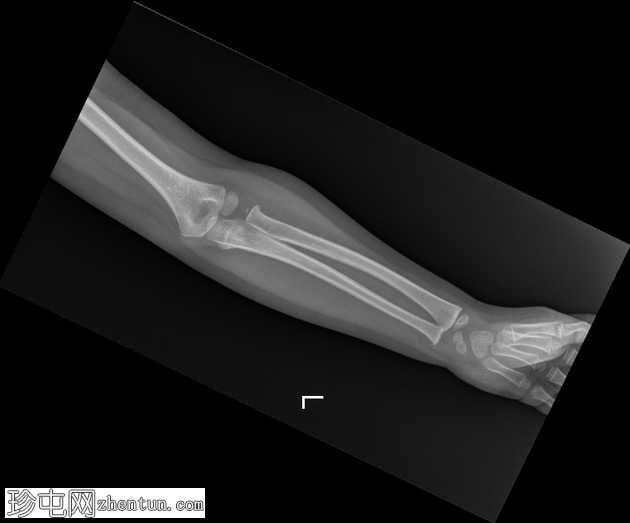

2.png

侧面

在正位片和侧位片上,桡骨近端干骺端可见轻微的皮质断裂和不规则,骨折线似乎向骺端延伸。

相关的脂肪垫征(可见前脂肪垫和帆状征,后脂肪垫阳性)进一步支持骨折后关节内积液的存在。

总体而言,骨性对线保持良好,无脱位迹象。

骨化中心与年龄相符。